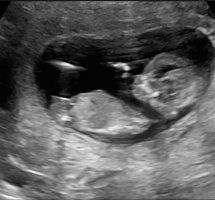

Jente 100%Klarer noen å se her? 13+2

Jeg tipper gutt, ser ut som en tapp på toppen av NUB

Det stemte! Det var en guttJeg tipper gutt, ser ut som en tapp på toppen av NUB

Så gøy og ha rett, gratulerer så myeDet stemte! Det var en gutt![]()

Du hadde rett, det var ei lita frøkenJente![]()